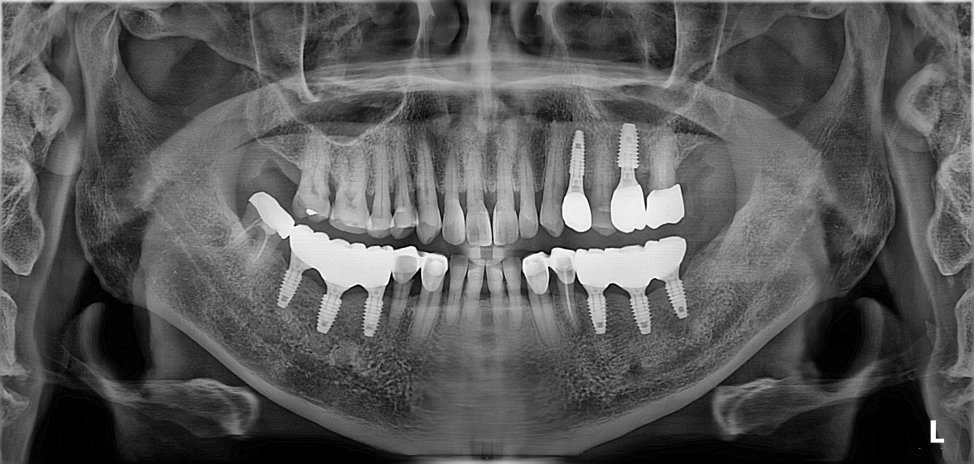

OPG - BEFORE

1. Phase 1: Posterior Stabilization: Dental implants were strategically placed in the posterior regions. These units served as the primary anchors for the new VDO, effectively "unlocking" the mandible from its retruded position.

• Stable Posterior Support: To place dental implants in the posterior segments, creating a firm foundation for the new occlusion.